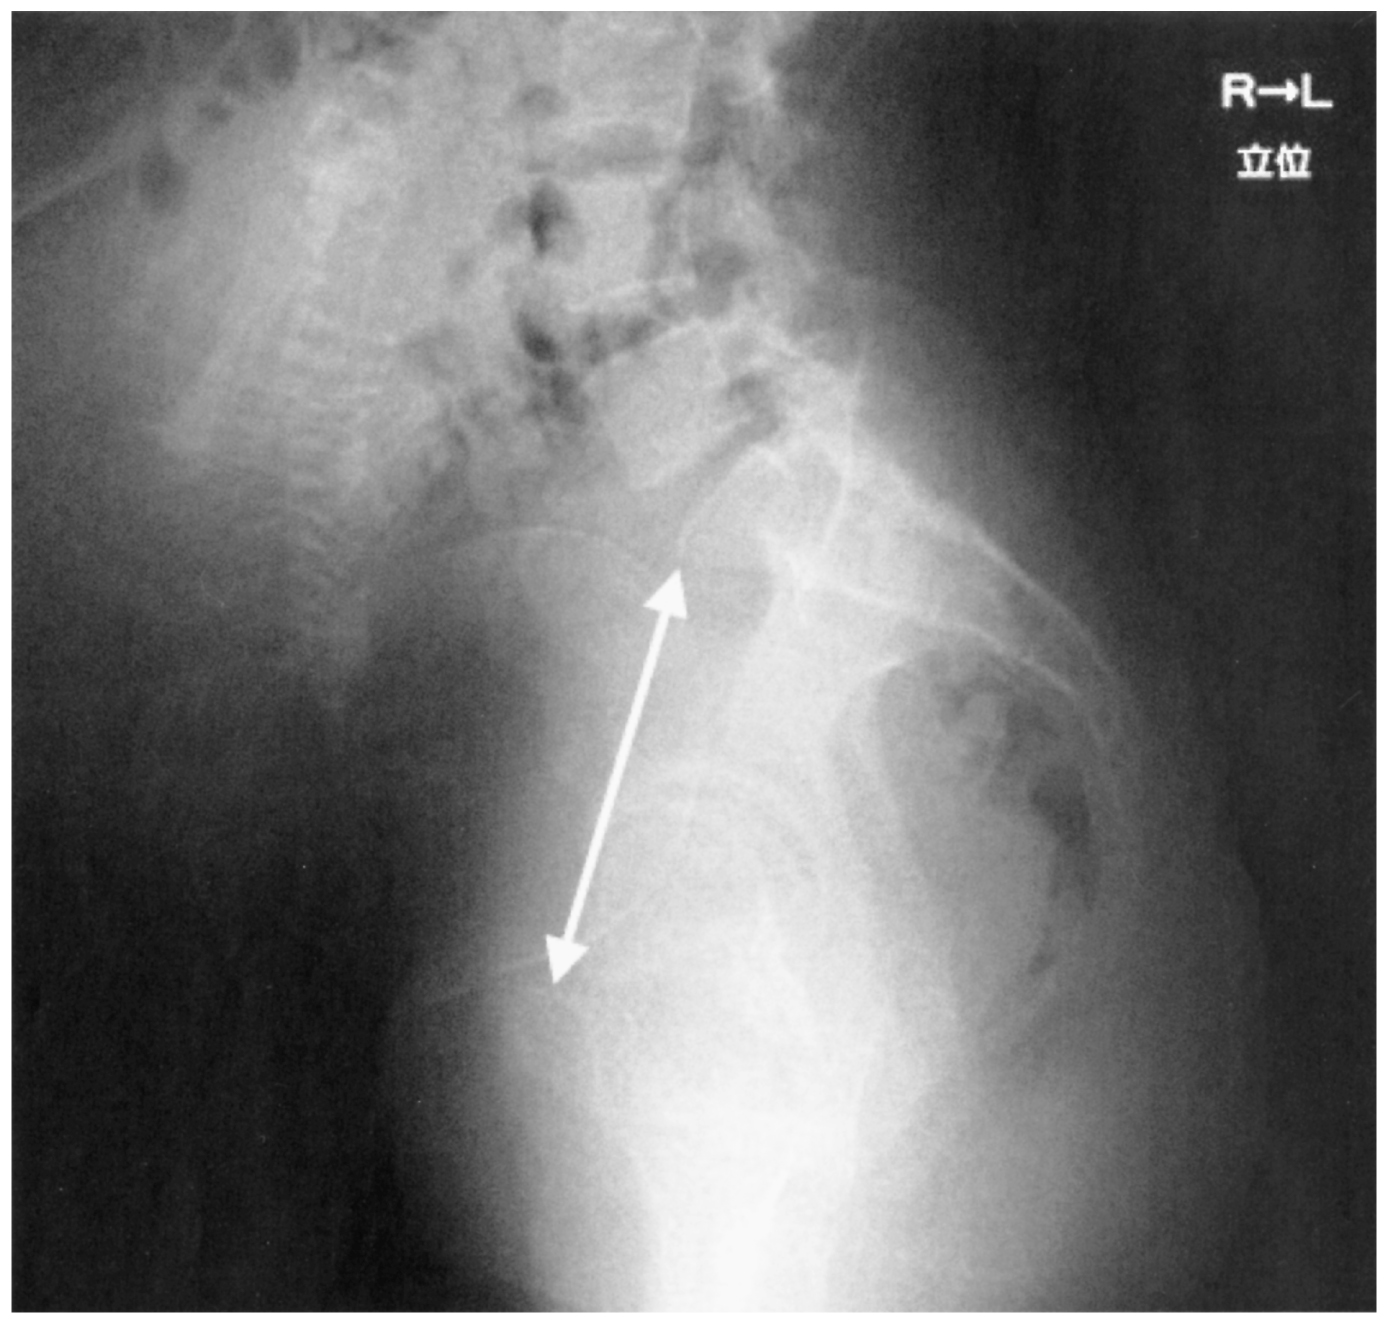

33歳の初妊婦(1妊0産)。妊娠38週4日,妊婦健康診査のために来院した。既往歴と家族歴とに特記すべきことはない。身長148cm,体重58kg。血圧128/64mmHg。尿所見:蛋白(-)。腹部超音波検査で児頭大横径98mm,推定胎児体重3,300g,羊水指数〈AFI〉9cm(基準5~24)である。子宮口は閉鎖。児頭は浮動している。骨盤エックス線写真を下に示す。産科的真結合線(矢印)は10.0cmである。